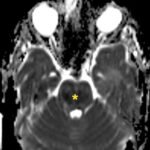

There is a growing body of literature and scientific discovery on pediatric autoimmune encephalitides. This is a heterogenous group of neuroinflammatory conditions leading to often perplexing acute and progressive neurologic and/or neuropsychiatric symptoms. This report demonstrates the evaluation and management of an adolescent with myelin-oligodendrocyte glycoprotein (MOG) antibody-associated fulminant acute disseminated encephalomyelitis (ADEM) in the context of current literature. The featured magnetic resonance imaging uniquely highlights progressive central nervous system lesions detected over the course of the first week of disease.